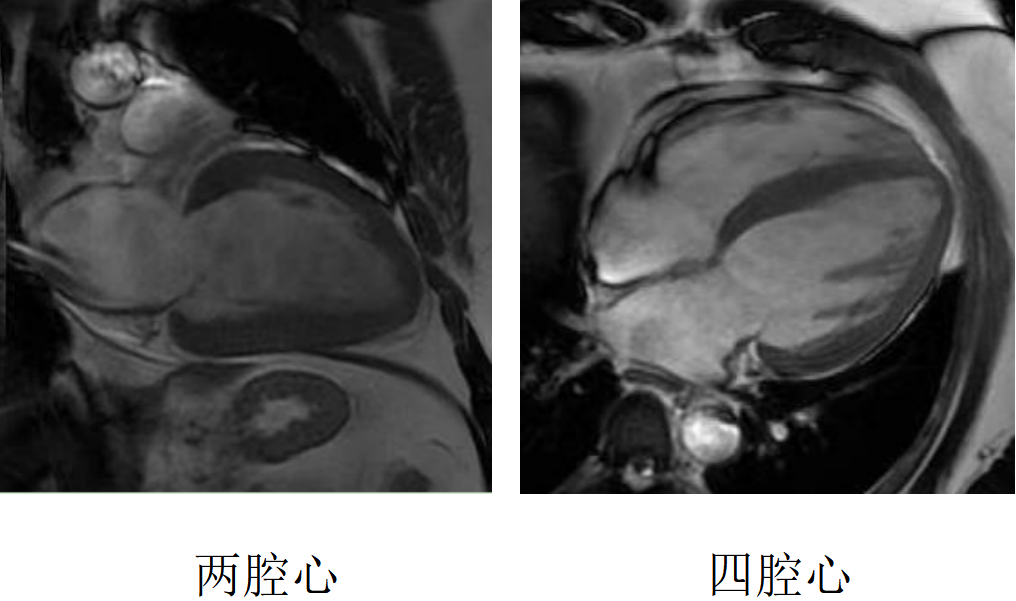

心臟磁共振被稱為心臟“一站式”檢查,通過多參數成像能夠對心臟的結構、功能、室壁運動、心臟瓣膜、心肌灌注和活性進行“一站式”評估。主要通過電影序列(短軸、兩腔心、四腔心、三腔心)、T2WI序列、首過灌注序列以及延遲強化序列對心臟進行綜合成像。